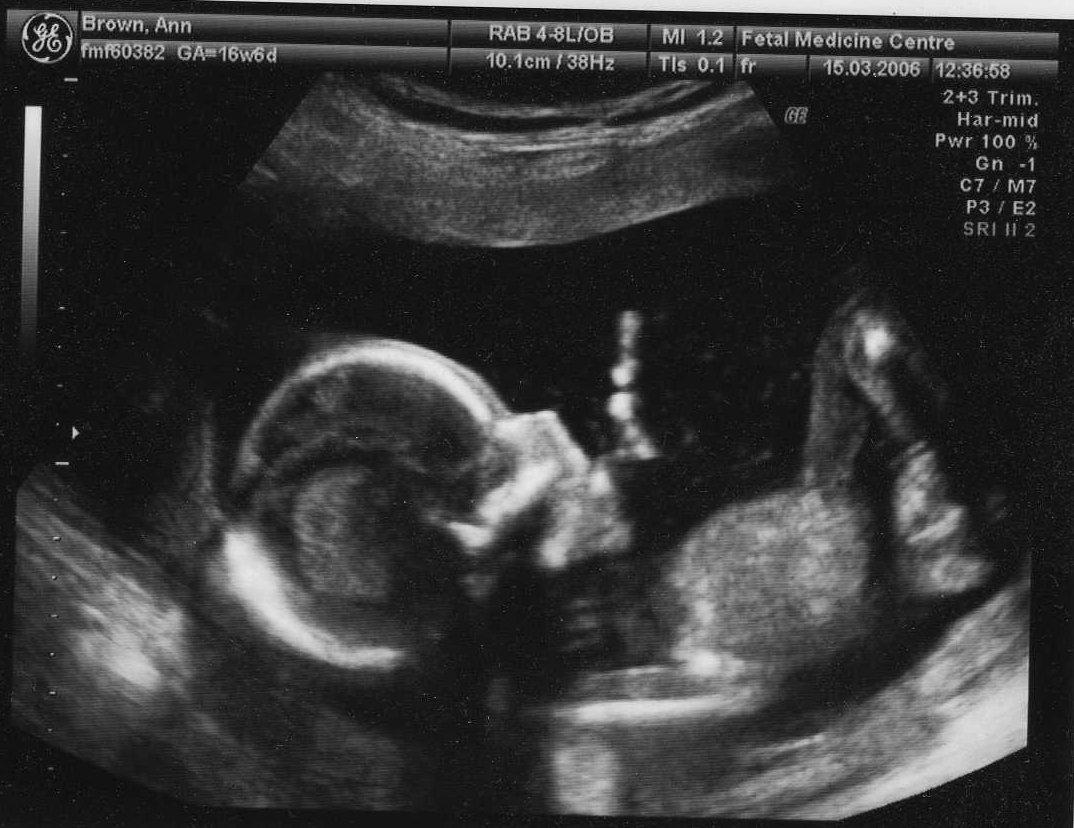

15th March 2006 (17 weeks) ... and taking it easy